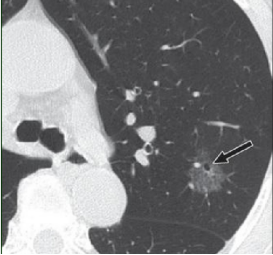

磨玻璃结节(GGN)是胸部CT上常见的影像学表现,因其与早期肺癌的关系而备受关注。近日,一项发表在《放射学》杂志的研究,通过对10年随访数据的分析,为磨玻璃结节的临床管理提供了重要参考。

1. CT随访是安全的:在磨玻璃结节出现实性成分前,CT随访是安全且合理的管理策略。

3. 关注实性成分:一旦磨玻璃结节出现实性成分,应考虑手术干预。